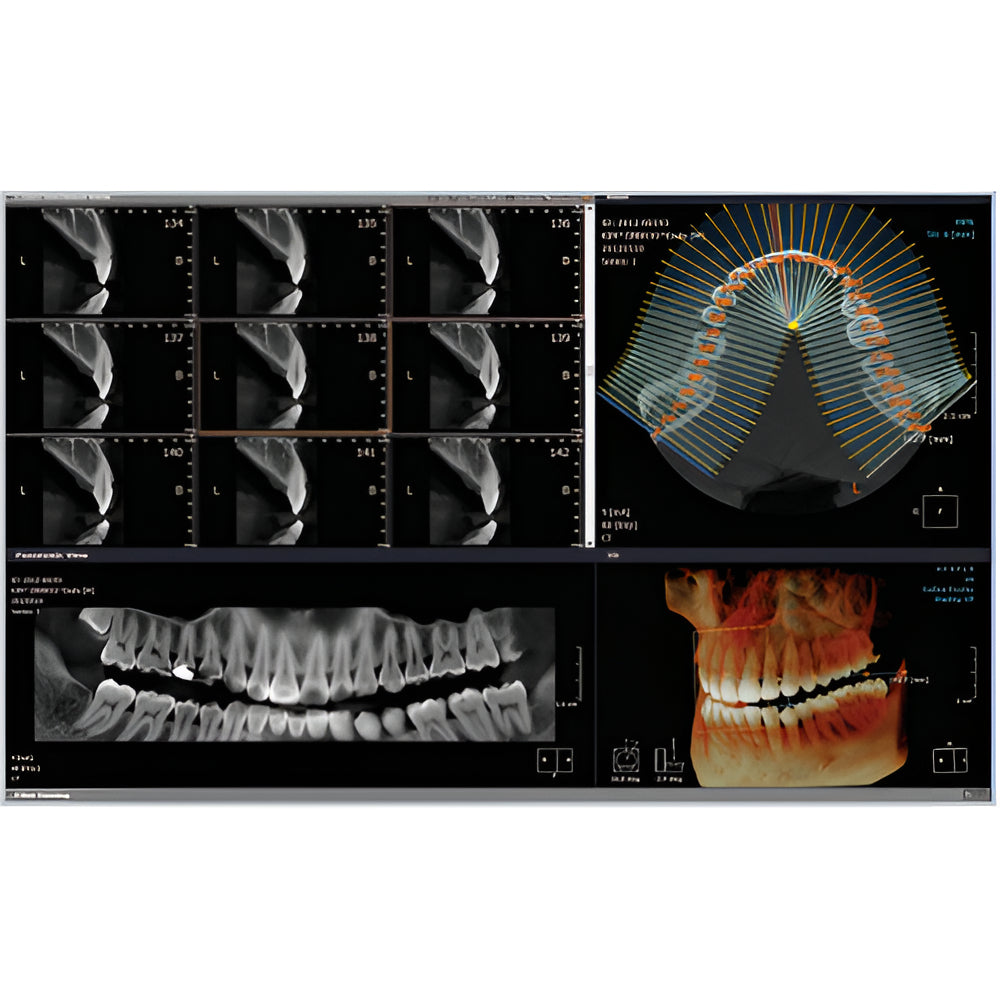

Rayscan Alpha brings another innovative technology with less Recon time and bigger FOV Size. And there are also new features – Fast scan mode, Object scan and Multi FOV.

- 2D/3D Imaging Software with License

- Panoramic

- Multiple Scan Modes